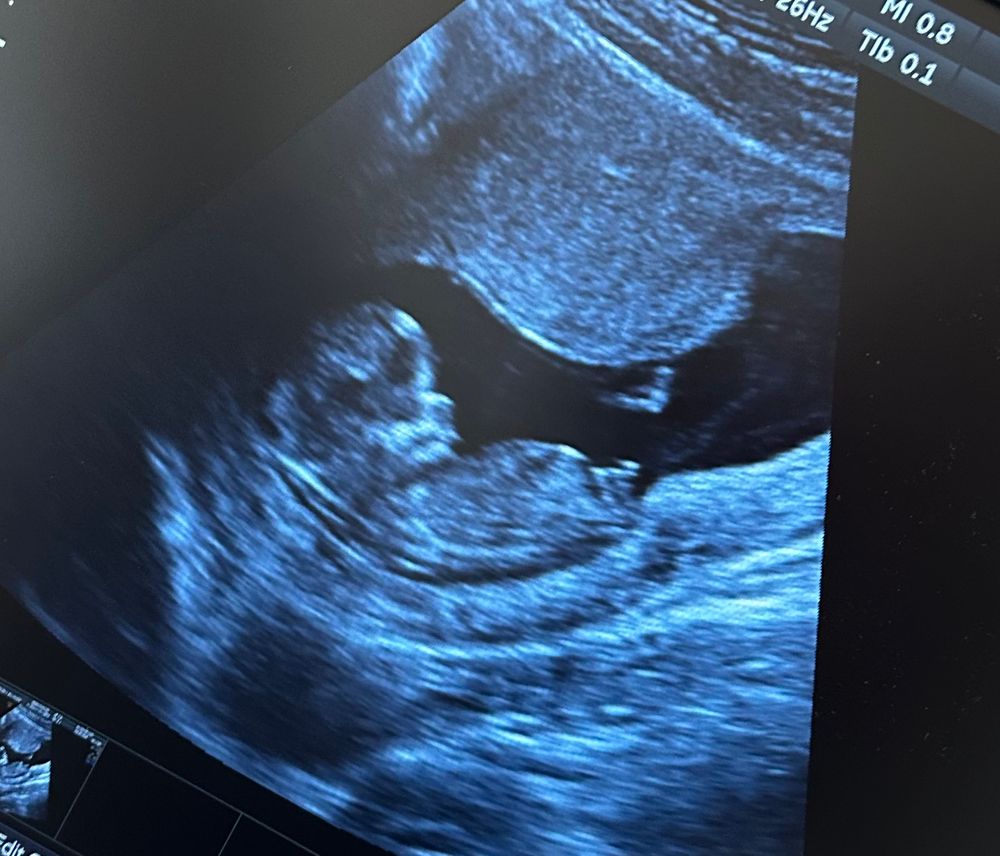

Половой бугорок. Первый скрининг

Осмотр в беременность, вопросыДевочки, ну что! Кто что видит?

тут нам 12 недель поставили. КТР 58 мм. Ручки ножки, очень активненько пузеныш двигается. Узи делали два через день. Поэтому картинки разные.

На верхнем девочка, на нижнем мальчик! Я угадала? 🤣

Кто бы что не видел- это не имеет никакого значения. На вашем сроке половые органы ребёнка недифференцированы, и положение полового бугорка еще среднее. Через две недели будет возможно предположить более обоснованно.